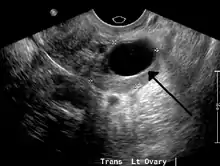

| A simple ovarian cyst of most likely follicular origin | |

Transvaginal ultrasonography of a hemorrhagic ovarian cyst, probably originating from a corpus luteum cyst. The coagulating blood gives the content a cobweb-like appearance.